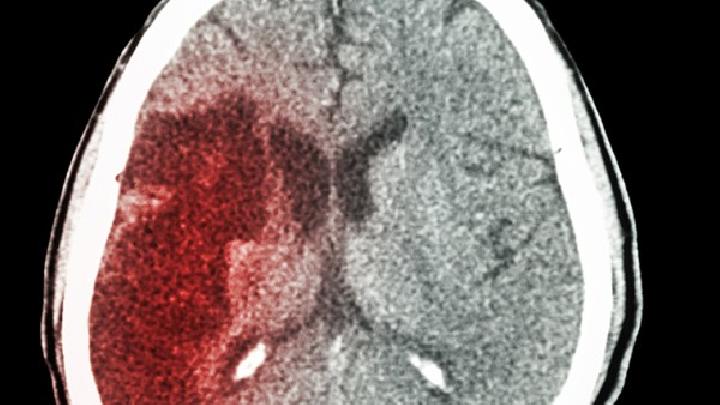

(5)硬膜下血肿:本症可急起或迟发,故列入急性期介绍。受伤后即出现头痛和嗜睡,但也可在数周或数月后发生,头痛呈波动性,时轻时重。可出现痴呆症状。迟发病例的特征是嗜睡、迟钝、记忆缺损和意识模糊。硬膜下血肿可出现痴呆的全部症状,偶尔呈现伴有运动性兴奋的急性谵妄状态。头痛常很严重,但也具有波动性,时轻时重。患者可以缺乏神经系统体征,仅表现轻度的头痛和波动性的精神紊乱。约有半数患者检出视盘水肿。脑脊液压力有轻度增高,蛋白定量增加,外观呈黄色,但脑脊液压力也可正常或低于正常。